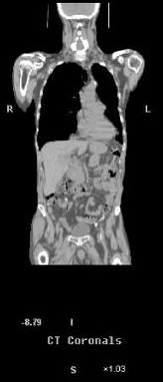

Fig. 7.

Rezulta ca PET si CT prezinta avantaje complementare, iar combinarea acestora crestepotentialul de localizare a leziunilor si reduce dificultatile de interpretare a imaginilor obtinute prin PET.

Fig. 8- Metastaze intrahepatice: imagini PET (18FFDG), CT si PET-CT.

sectiuni transversale (stanga) si sectiuni coronale (dreapta)